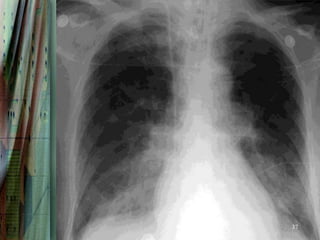

Radiography

Chest radiography is helpful in distinguishing CPE from other

pulmonary causes of severe dyspnea.

Features that suggest CPE rather than NCPE and other lung

pathologies include the following:

•   Enlarged heart

•   Inverted blood flow

•   Kerley lines

•   Basilar edema (vs diffuse edema)

•   Absence of air bronchograms

•   Presence of pleural effusion (particularly bilateral and

36

symmetrical pleural effusions)

37

38